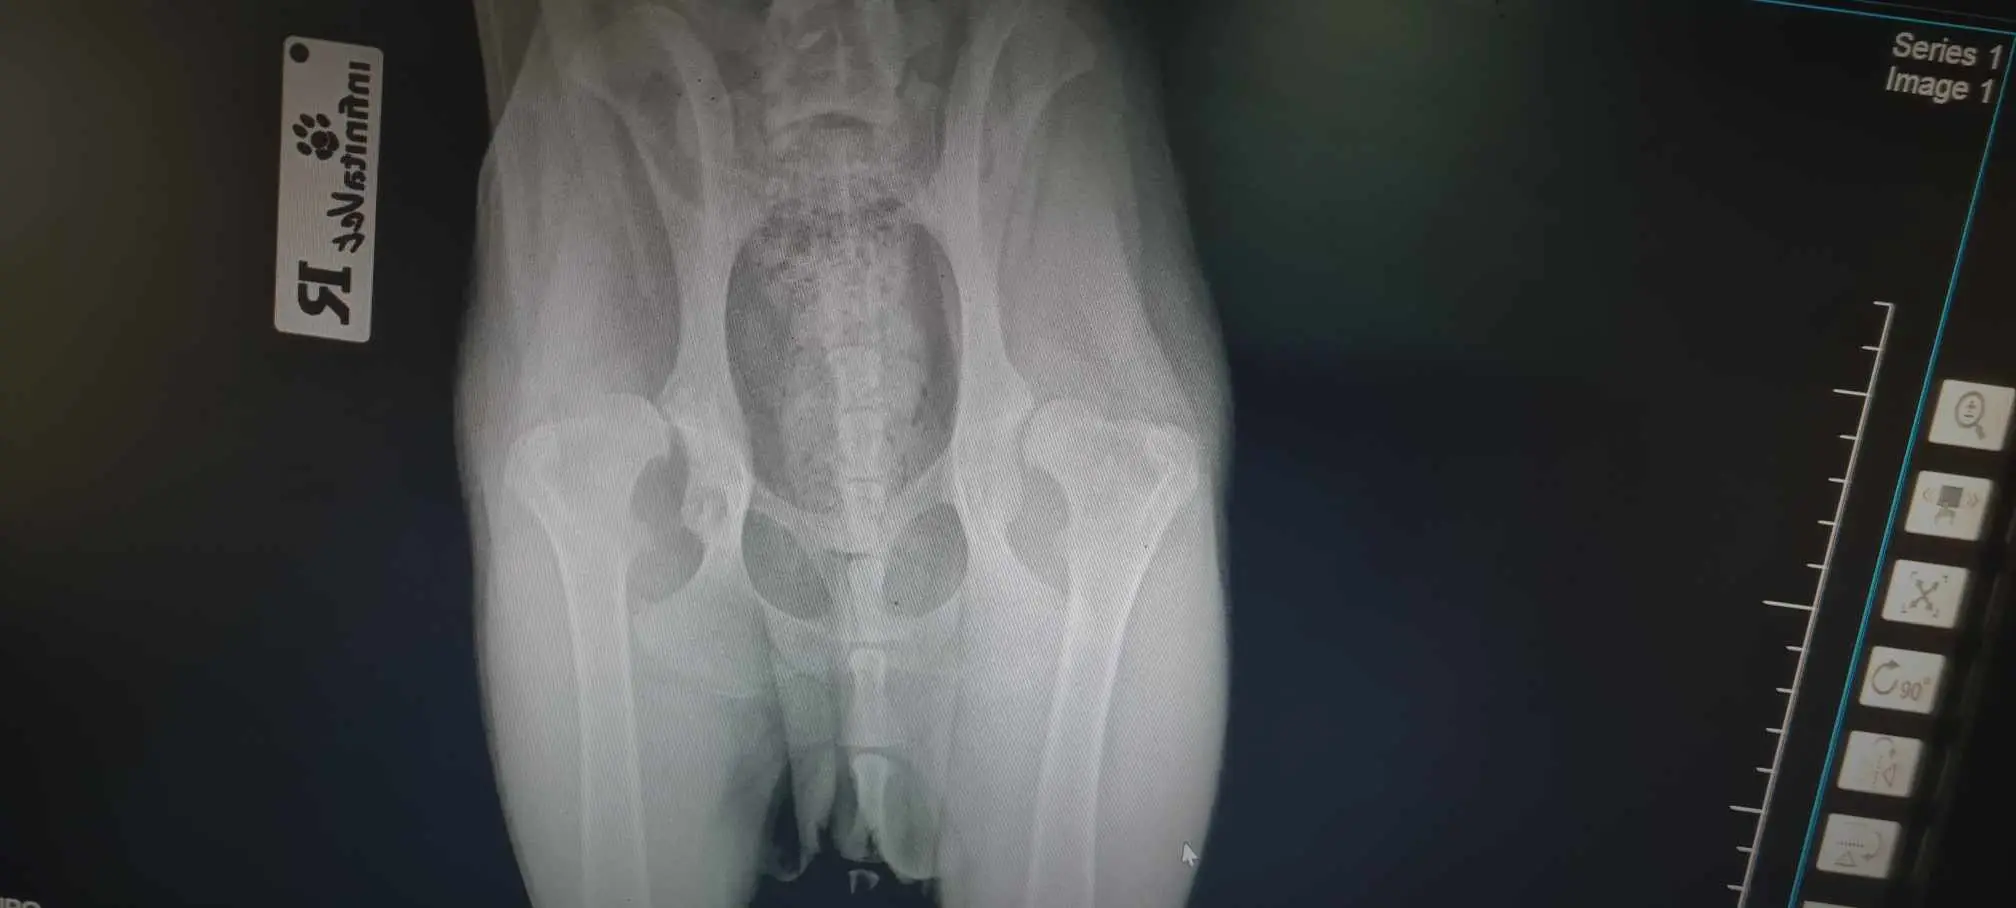

Помогни на Толя и Джиото да тичат без болка

Помогни на Толя и Джиото да тичат без болка